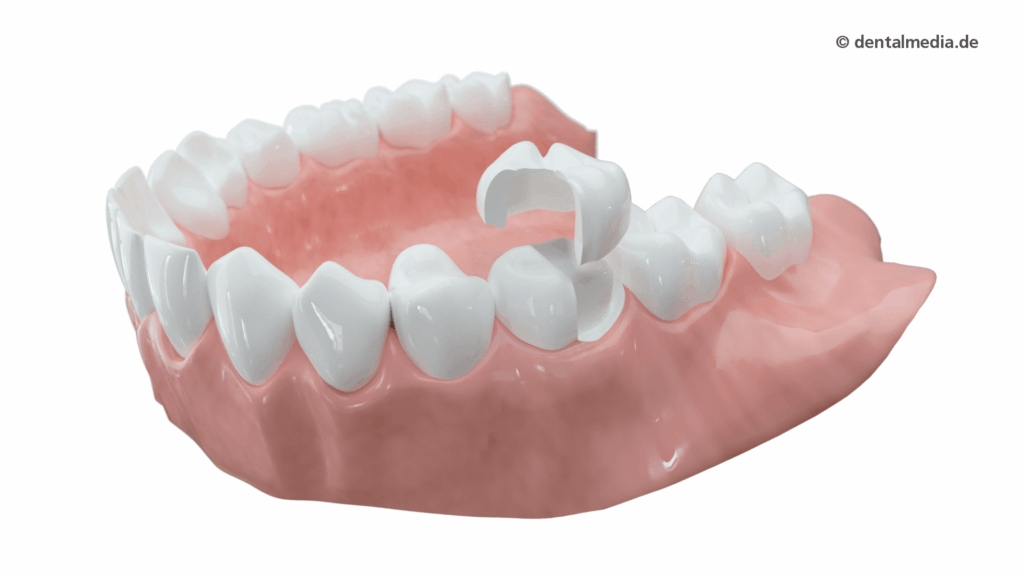

Kronen-Indikationen: Substanzverlust, Frakturen & Endo-Zähne

Kronen kommen zum Einsatz bei stark zerstörter Zahnsubstanz, nach großen Füllungen, Frakturen oder endodontischer Versorgung. Sie ummanteln den Zahn, stabilisieren ihn dauerhaft und stellen Kaufläche, Kontaktpunkte und Ästhetik wieder her – im Front- wie Seitenzahnbereich, je nach Materialwahl.

Zirkon bietet hohe Biegefestigkeit im Seitenzahnbereich; e.max brilliert im Frontzahnbereich. Digitale Bissdaten, Face-Scan und Farbnahme erhöhen Vorhersagbarkeit. Individuelle Schichtung, polierte Kontaktflächen und kontrollierte Okklusion sorgen für Komfort, Langlebigkeit und Gewebeverträglichkeit.